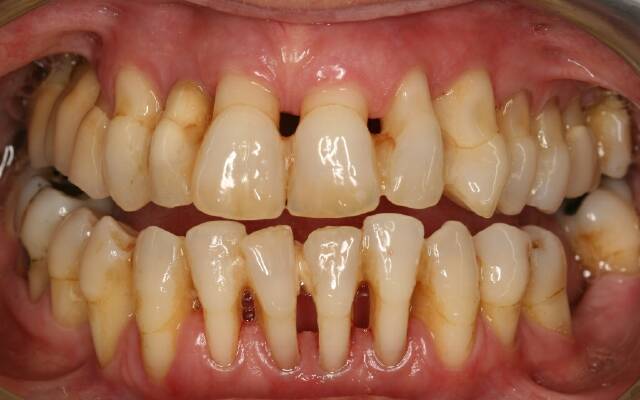

Фото

Симптомы пародонтоза

Клинические проявления пародонтоза зависят от стадии и тяжести заболевания. На начальных этапах симптомы могут быть едва заметными, но со временем усиливаются, создавая проблемы для пациента.

- Тяжелая степень – зубы выступают из десны более чем наполовину. Наблюдается значительная подвижность зубов из-за атрофии костных перегородок. Промежутки между зубами увеличиваются, что способствует накоплению остатков пищи и образованию зубного камня. Это последняя стадия, которая может привести к потере зубов. На рентгеновских снимках видно неравномерное сглаживание костных перегородок.

Одной из особенностей пародонтоза, отличающей его от пародонтита, является отсутствие воспалительных симптомов на всех стадиях. Десны сохраняют бледно-розовый цвет и могут не иметь патологических зубодесневых карманов.